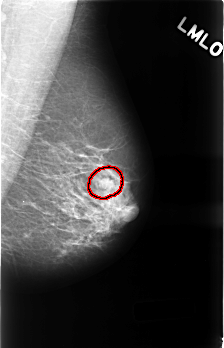

C_0491_1.LEFT_MLO

LEFT_MLO LINES 4512 PIXELS_PER_LINE 2912 BITS_PER_PIXEL 12 RESOLUTION 50 OVERLAY

FILE: C_0491_1.LEFT_MLO.OVERLAY

TOTAL_ABNORMALITIES 1

ABNORMALITY 1

LESION_TYPE MASS SHAPE LOBULATED MARGINS CIRCUMSCRIBED

ASSESSMENT 4

SUBTLETY 5

PATHOLOGY BENIGN

TOTAL_OUTLINES 1

BOUNDARY